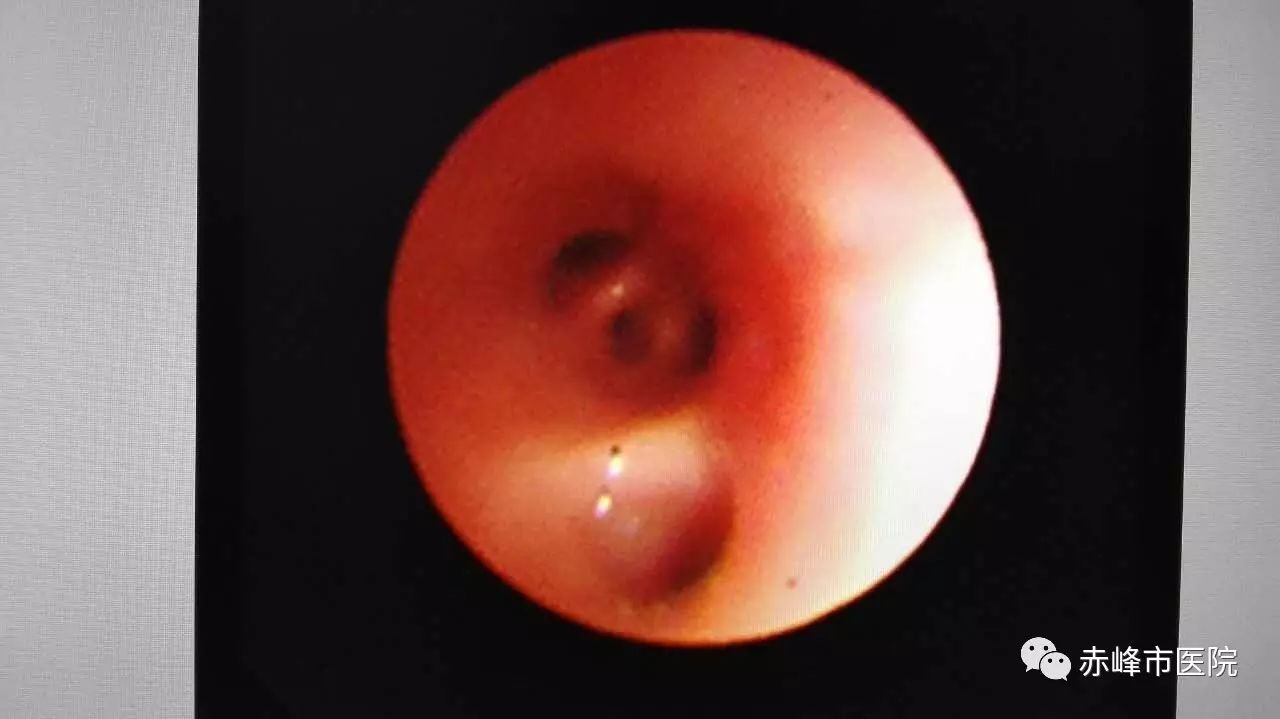

患儿完全阻塞的左肺上下支气管

入院后的第二天下午,在杨淑兰主任的带领下,由儿科副主任萨初然贵、主治医师尹凤蕊、住院医师王方成、护师李月荣组成的支气管镜治疗小组在儿科PICU,利用呼吸机辅助下经气管插管、用仅能通过的先端2.8mm的支气管镜进行镜下检查,镜子进入患儿左主气道后发现左侧主气道被痰栓完全堵塞,而且痰栓像树枝一样形成支气管塑形,导致患儿左肺完全不张、迅速出现呼吸衰竭。